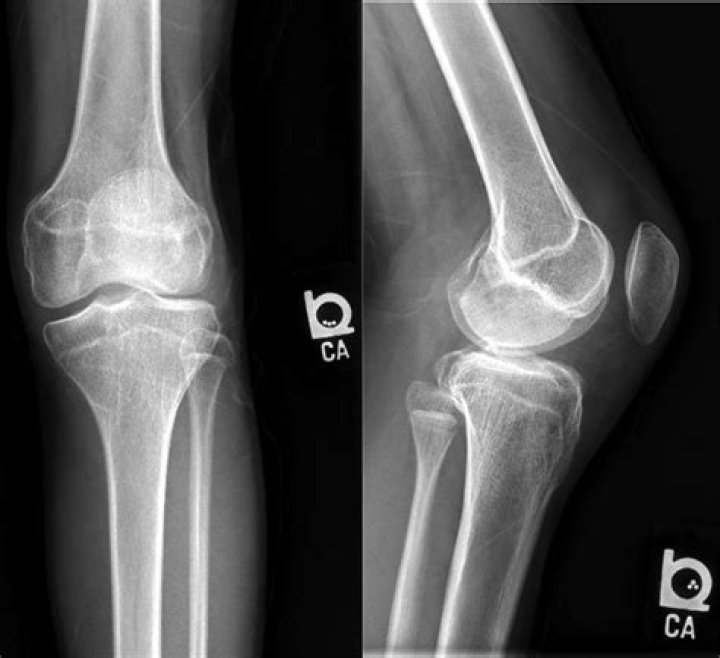

Tumoral calcinosis (TC) is a rare clinical and histopathologic syndrome characterized by calcium salt deposition in different peri-articular soft tissue regions[1,2].

Tumoral calcinosis may be genetic, the result of prior traumatic injury, or the result of a metabolic derangement, most commonly chronic renal failure, which accounts for approximately 23% of cases. Onset is typically in the second decade of life, with a reported increased frequency in African Americans.

Tumoral calcinosis is a familial disease, usually associated with hyperphosphatemia, that is manifested by the deposition of calcific masses around major joints. Surgical excision of the masses has been the only partially effective treatment.